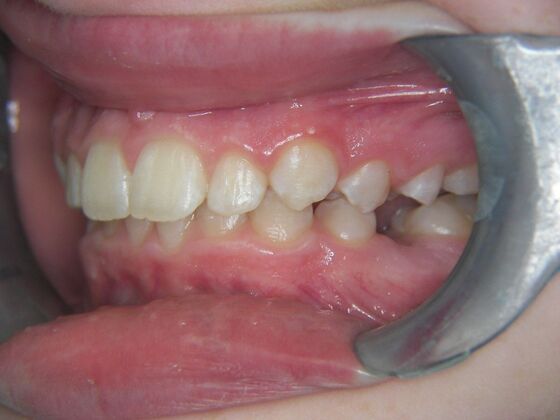

Patient is 9 years old and presents with 100% overbite and blocked out upper and lower lateral incisors. Both upper central incisors are palatally inclined causing a lack of space available for most anterior teeth. Advised her parents that she needs Phase I Interceptive Orthodontic treatment to provide room for all upper and lower front teeth. Phase I treatment was begun and finished, then began Phase II treatment shortly thereafter to finalize case. Removable retainer were fabricated for retention.